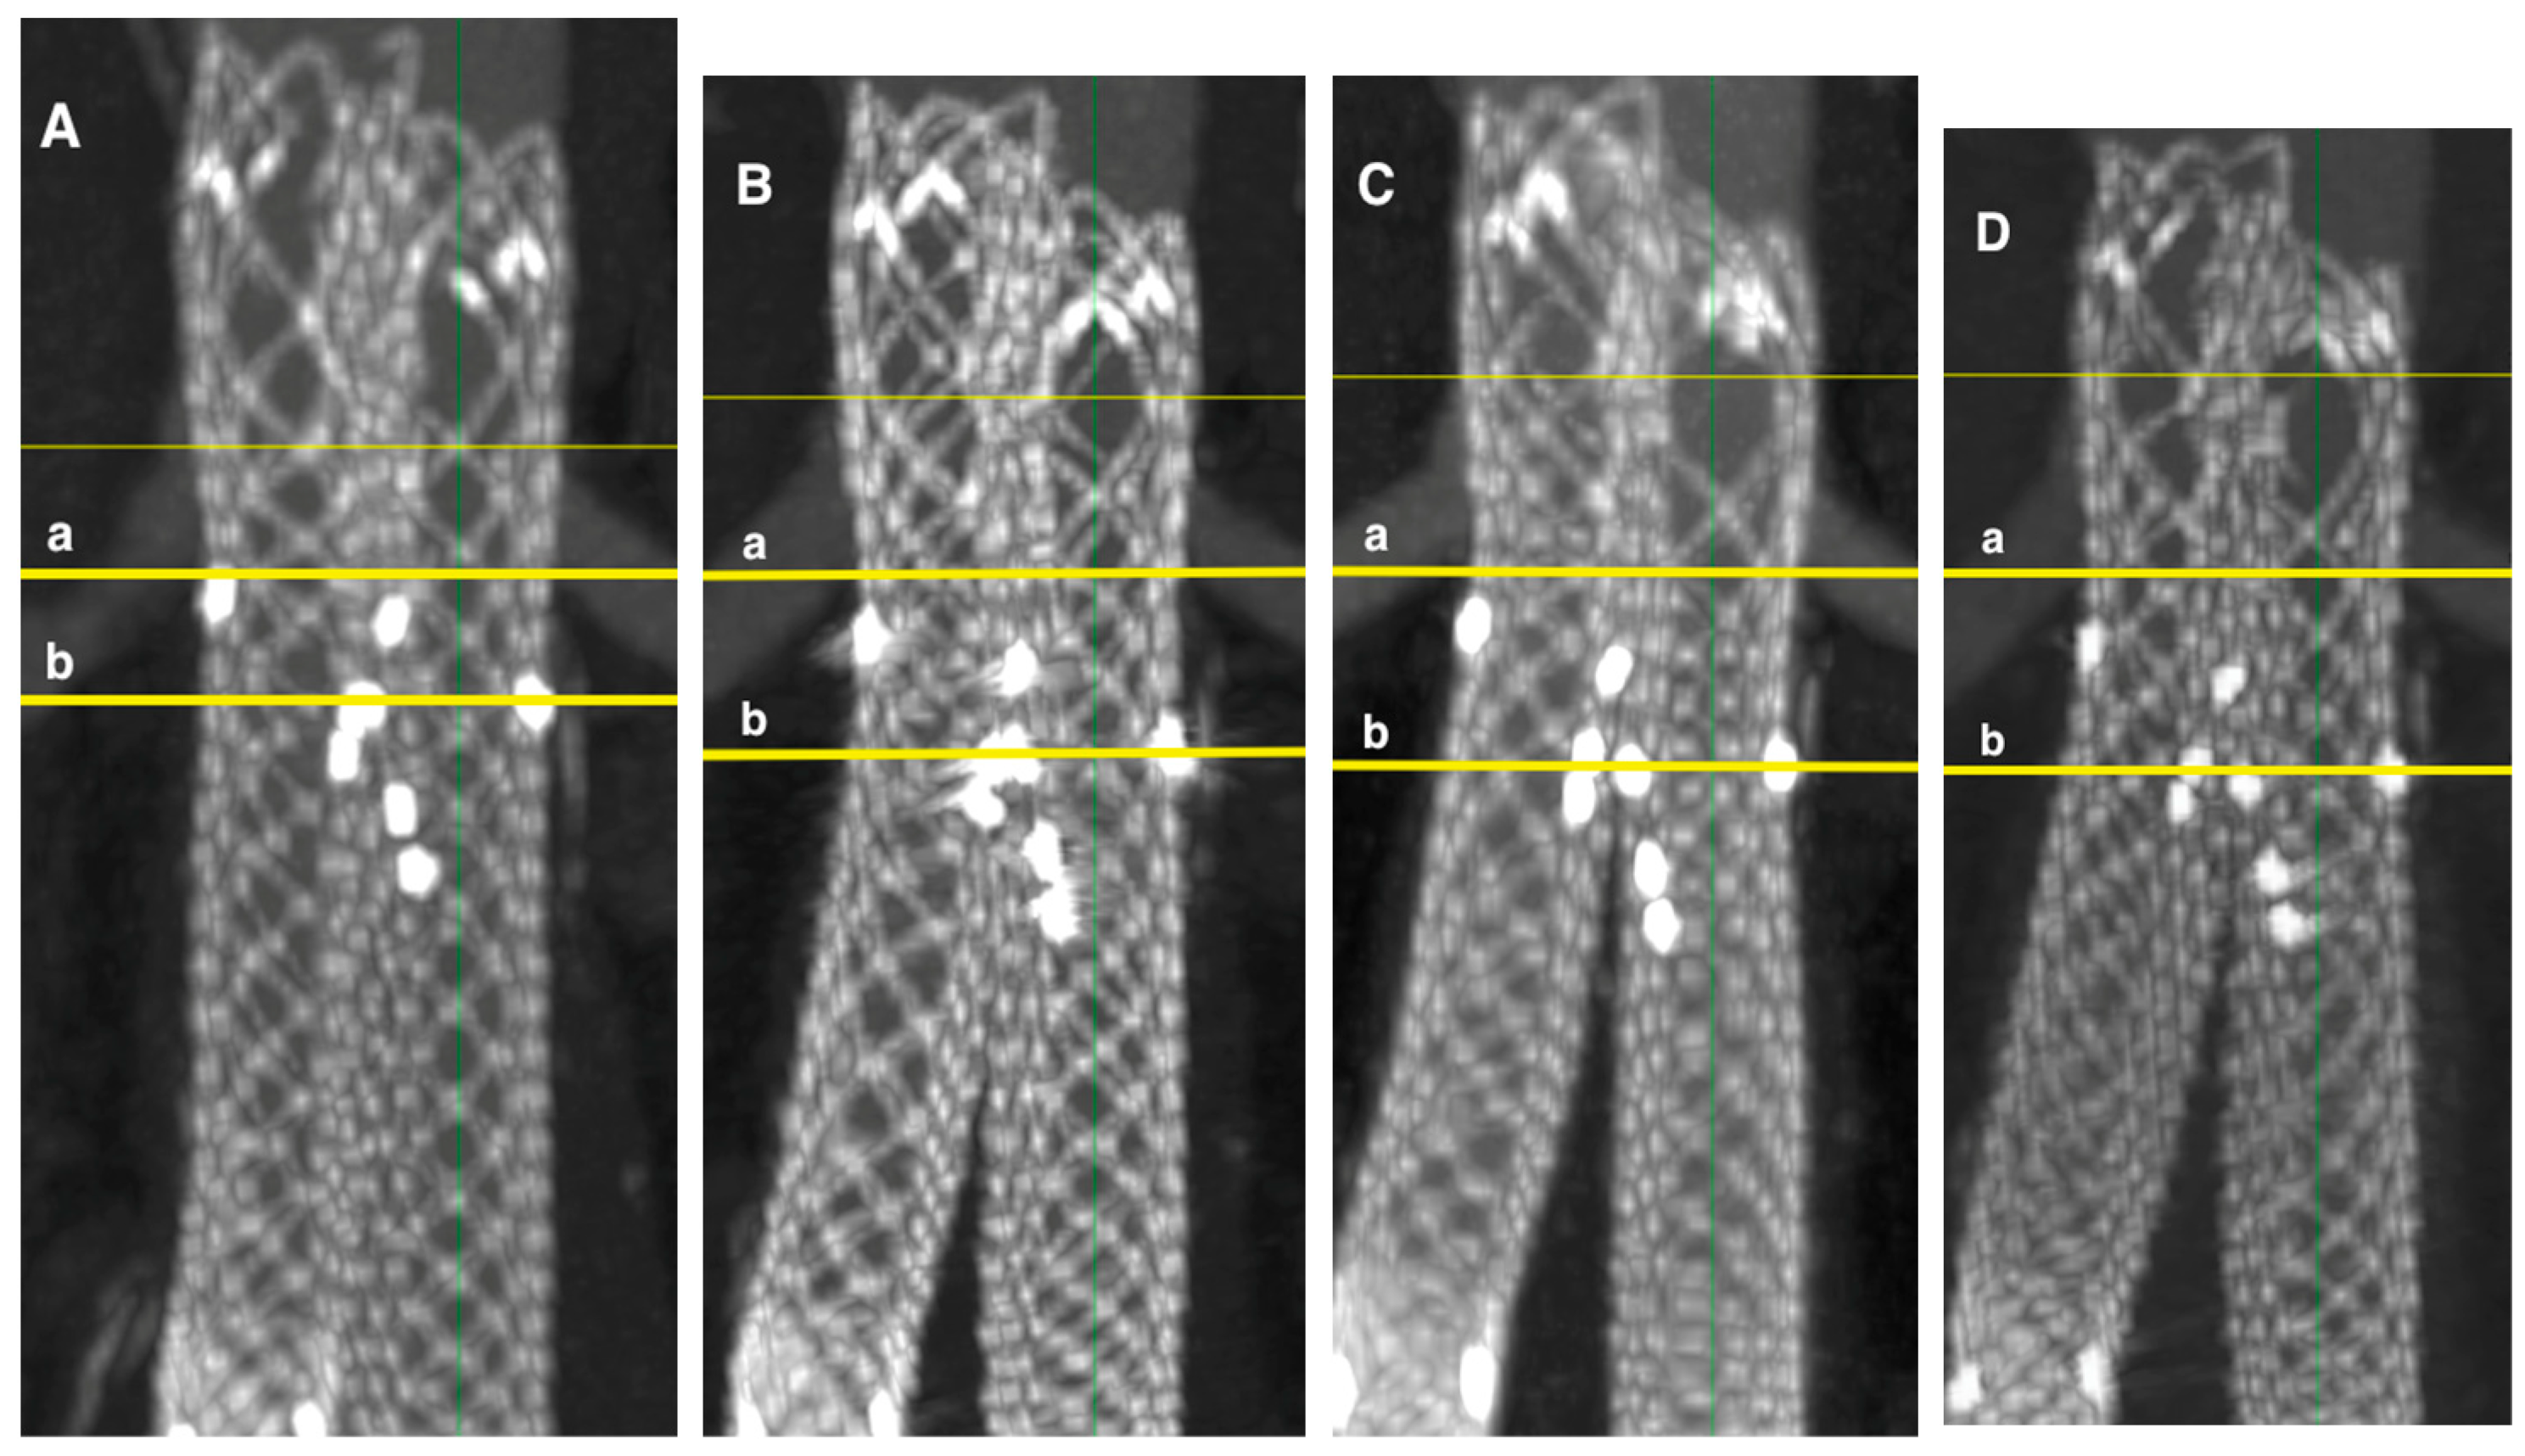

The mean total stent graft shortening one year after EVAR, compared to the first CT scan follow-up one month after EVAR, was 4 ± 3 mm. The total stent graft shortening two years after EVAR was 7 ± 5 mm, and three years after EVAR was 9 ± 6 mm (Figure 7).

Stent graft shortening greater than 10 mm, compared with the first CT scan follow-up one month after EVAR, was observed in 3% of stent grafts (2/63) after one year, 27% (13/48) after two years, and 50% (8/16) after three years.

The total shortening of the ALTURA™ stent graft system at one, two, and three years after implantation was statistically significant compared to the first follow-up one month after EVAR (p < 0.001). Significant shortening was observed in the iliac extension, while changes in the aortic stent graft were not statistically significant (Table 4).

Specifically, aortic stent graft shortening was 1 ± 3 mm after one year, 2 ± 4 mm after two years, and 4 ± 4 mm after three years. The iliac extensions shortened by 4 ± 3 mm after one year, 6 ± 4 mm after two years, and 8 ± 4 mm after three years. The shortening of the overlapping zone and iliac extensions was statistically significant over the three-year period (p < 0.002).

Figure 7. Shortening of Altura stent graft. (A)—1st month follow-up with stent graft length 17.3 cm, (B)—1st year—16.6 cm, (C)—2nd year—15.9 cm (D)—3rd year—15.7 cm, a—aortic stent graft renal artery radiopaque marker, b—end of the iliac stent graft.